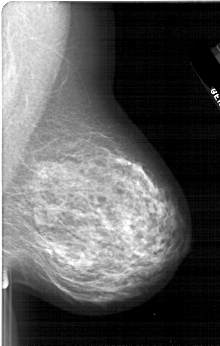

A_1668_1.LEFT_MLO

LEFT_MLO LINES 6061 PIXELS_PER_LINE 3991 BITS_PER_PIXEL 12 RESOLUTION 43.5 OVERLAY